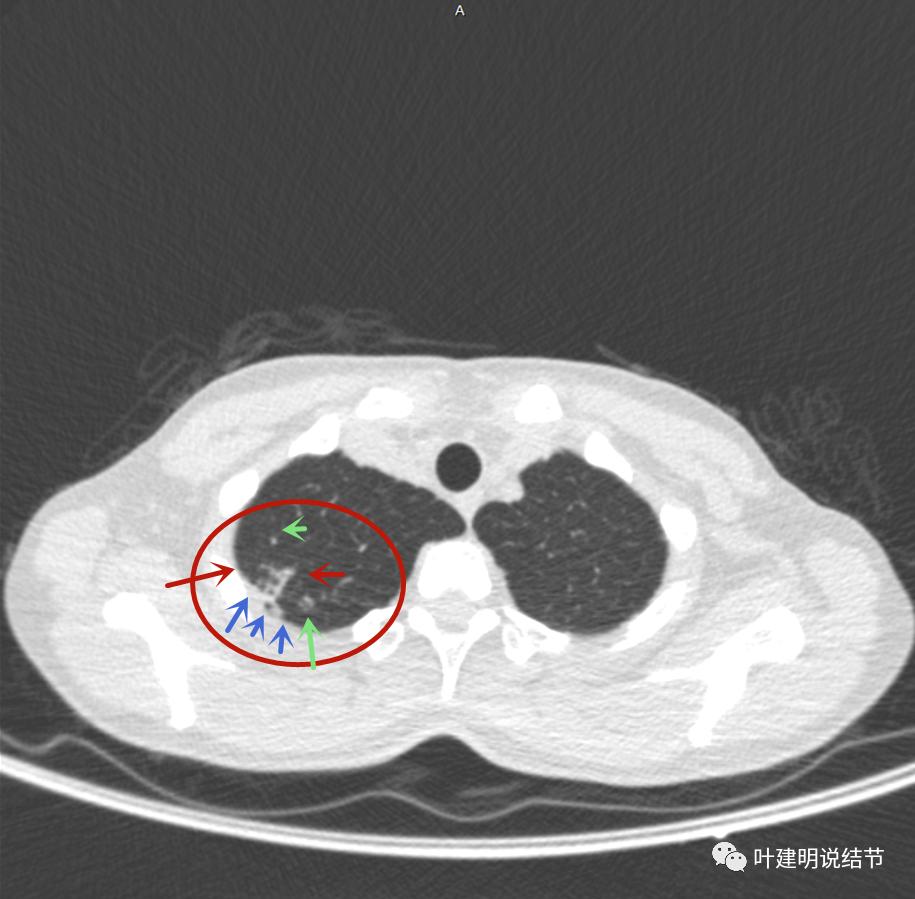

主病灶出现,粉色箭头示病灶密度较高,边上有磨玻璃影,甚淡(砖色箭头)

病灶有空洞(黄色箭头),主病灶边上见条索状高密度影(细红色箭头),邻近胸膜有粘连(蓝色箭头)